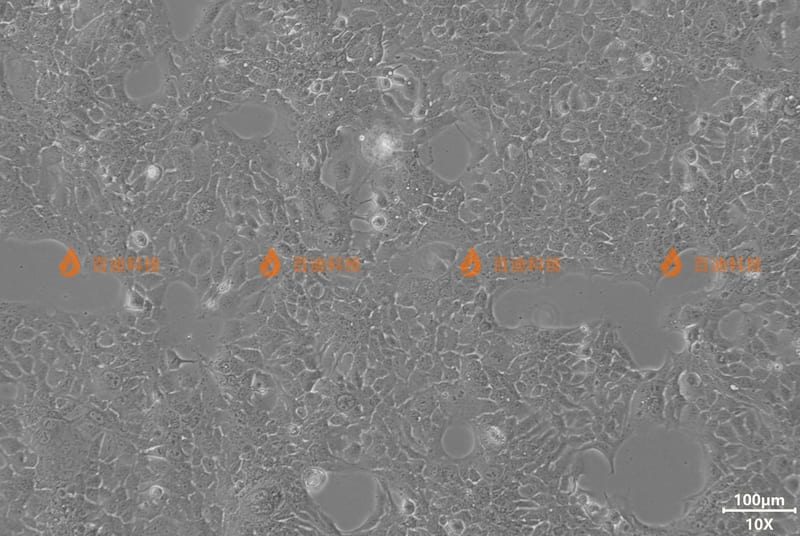

HCC827(人非小细胞肺癌细胞)

HCC827